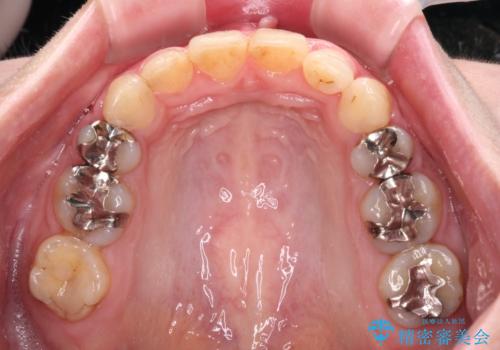

- 他院で抜歯矯正を終えた後、銀色の目立つ奥歯を白くしたいとのことで来院された患者様です。

既にセラミッククラウンが装着されている歯もありますが、不自然な色合いや黒い縁も気になるので、一斉に補綴治療をして統一感を持たせることとしました。